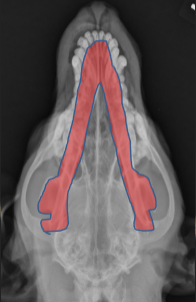

ID Radiographic View

Open Mouth VD view of Nasal Cavity

ID

Ethmoid Turbinates

Maxillary Turbinates

VOmer Bone

Palantine Foramen